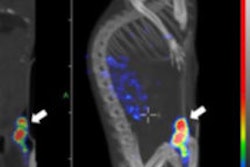

Lutetium-177 PSMA-617 radionuclide therapy has been shown to reduce tumor burden and induce prostate-specific antigen remission in patients with metastatic advanced prostate cancer. Image courtesy of JNM.

Lutetium-177 PSMA-617 radionuclide therapy has been shown to reduce tumor burden and induce prostate-specific antigen remission in patients with metastatic advanced prostate cancer. Image courtesy of JNM.The 145 subjects (median age, 73 years; range, 43-88 years) were treated with Lu-177 PSMA-617 between February 2014 and July 2015 with one to four therapy cycles. A total of 248 therapy cycles were performed on the patients.